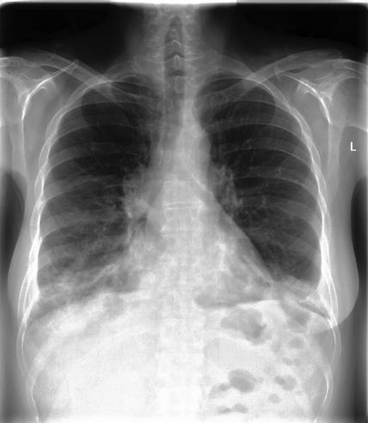

We introduce a novel Region-based contrastive pretraining for Medical Image Retrieval (RegionMIR) that demonstrates the feasibility of medical image retrieval with similar anatomical regions. RegionMIR addresses two major challenges for medical image retrieval i) standardization of clinically relevant searching criteria (e.g., anatomical, pathology-based), and ii) localization of anatomical area of interests that are semantically meaningful. In this work, we propose an ROI image retrieval image network that retrieves images with similar anatomy by extracting anatomical features (via bounding boxes) and evaluate similarity between pairwise anatomy-categorized features between the query and the database of images using contrastive learning. ROI queries are encoded using a contrastive-pretrained encoder that was fine-tuned for anatomy classification, which generates an anatomical-specific latent space for region-correlated image retrieval. During retrieval, we compare the anatomically encoded query to find similar features within a feature database generated from training samples, and retrieve images with similar regions from training samples. We evaluate our approach on both anatomy classification and image retrieval tasks using the Chest ImaGenome Dataset. Our proposed strategy yields an improvement over state-of-the-art pretraining and co-training strategies, from 92.24 to 94.12 (2.03%) classification accuracy in anatomies. We qualitatively evaluate the image retrieval performance demonstrating generalizability across multiple anatomies with different morphology.